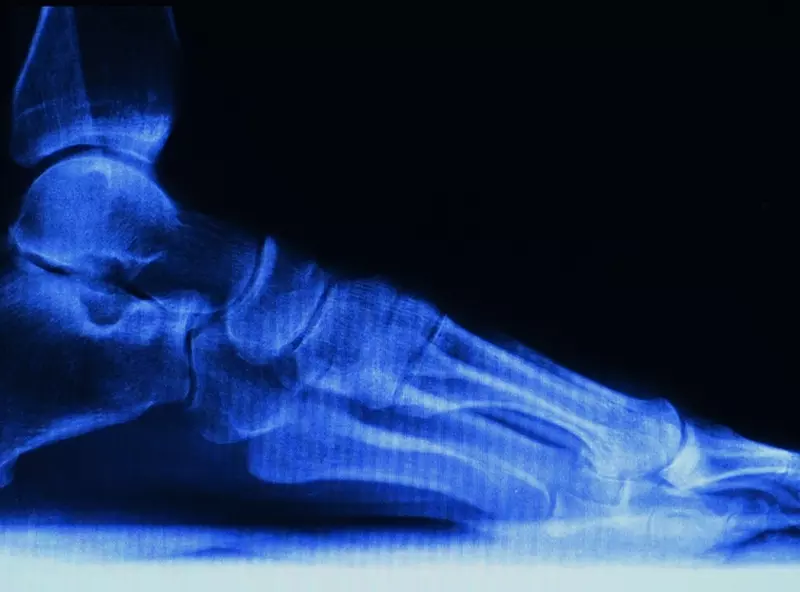

Strefa przejściowa między odcinkiem szyjnym i piersiowym kręgosłupa, zwana krócej przejściem szyjno-piersiowym (PSP), stanowi unikatowy rejon zarówno pod względem budowy anatomicznej, jak i mnogości zadań, jakim musi sprostać. Jest to obszar kluczowy dla unerwienia i unaczynienia kończyn górnych, strefa przejścia elementów układu trzewnego z szyi do śródpiersia, a także miejsce spływu limfatycznego z całego ciała. Strefa ta, narażona na przeciążenia mechaniczne i dysfunkcje jako przejściowa między bardzo mobilnym odcinkiem szyjnym i sztywnym odcinkiem piersiowym, poddawana często emocjonalnym wzorcom napięciowym (somatyzacji emocjonalnej), modulowanym m.in. przez bliską obecność elementów układu autonomicznego, jest często lekceważonym lub nierozpoznanym źródłem dolegliwości bólowych.

Ściśle rzecz ujmując, anatomiczne PSP tworzy ruchome połączenie segmentów C7 i Th1 kręgosłupa. Jednak myśląc o odcinku przejściowym szyjno-piersiowym w kategoriach funkcjonalnych, odnosimy się umownie do dwóch dolnych kręgów szyjnych i czterech górnych kręgów piersiowych. Staw C6/C7 stanowi pierwszy segment sąsiadujący od góry z anatomicznym PSP i o ile prezentuje typowy dla odcinka szyjnego kształt trzonów kręgowych, to już zmieniony (bardziej pionowy) przebieg powierzchni stawowych jest typowy dla odcinka piersiowego. Unerwienie stawu C7/Th1 pochodzi częściowo z gałązek przyśrodkowych nerwów rdzeniowych wychodzących piętro wyżej, a więc z poziomu C6/C7. Segment Th4 zaś jest umowną funkcjonalną granicą PSP ze względu na zasięg przyczepów mięśni schodzących z odcinka szyjnego do piersiowego (np. mięsień dźwigacz łopatki i mięśnie płatowate), co powoduje, że ruch odcinka szyjnego przenosi się na górne cztery segmenty piersiowe. Poziom Th 4 jest również umowną granicą śródpiersia górnego ograniczonego od przodu mostkiem i jego połączeniem z pierwszym żebrem i obojczykiem. W obręb górnego śródpiersia wchodzą tak ważne struktury anatomiczne, jak: łuk aorty i naczynia od niego odchodzące, żyła główna górna, osklepek opłucnej, szczytowe płaty płuc, górny odcinek tchawicy i przełyku, nerwy błędne i przeponowe, zwoje współczulne oraz liczne naczynia i węzły chłonne. To na tym odcinku zachodzi przejście fizjologicznych krzywizn kręgosłupa – lordozy szyjnej w kifozę piersiową, a w sytuacji wad posturalnych jest to również strefa przedniego przesunięcia głowy względem tułowia, co powoduje kaskadę negatywnych konsekwencji w aspekcie drenażu żylno-limfatycznego. Strefa PSP to również wielowarstwowy układ powięzi schodzących z odcinka szyjnego do klatki piersiowej. Wśród nich należy wymienić: